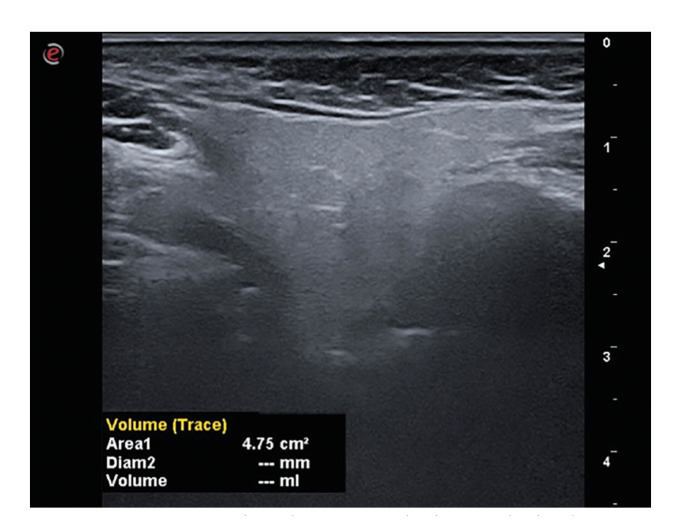

Material and methods: The parotid glands of 38 individuals with diabetes and 38 healthy controls were examined bilaterally using ultrasound to assess parameters of volume, stiffness and microvascularity.

Results: A statistically significant increase in parotid gland volume and a statistically significant decrease in microvascularity were observed in diabetic patients. Furthermore, a statistically significant increase in parotid gland volume was noted in diabetic individuals who were using antidiabetic drugs in comparison to non-users. A significant negative correlation was identified between the duration of exposure to diabetes and microvascularity.

Conclusions: Ultrasonographic imaging can be used to assess the dimensions and microvascularity of the parotid gland.